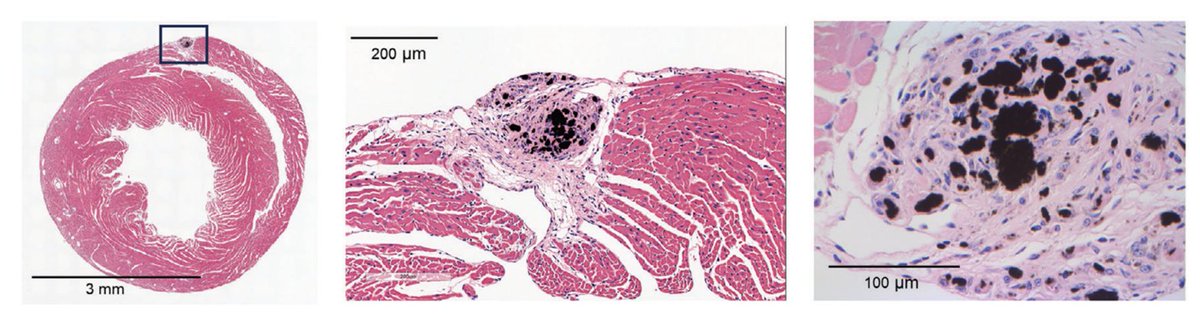

Carbon nanotubes create lesions that closely resemble sarcoid. Sixty days after injecting them into the heart, we observed typical sarcoid granuloma histiocytes co-localizing with the nanotubes (black markings). 🔗doi: 10.1002/adbi.202400238

Exciting news! This study addresses a critical gap in cardiac sarcoidosis research by exploring the use of stressors like carbon nanotubes and transverse aortic constriction to develop one of the world’s first animal models. 🔗doi: 10.1002/adbi.202400238